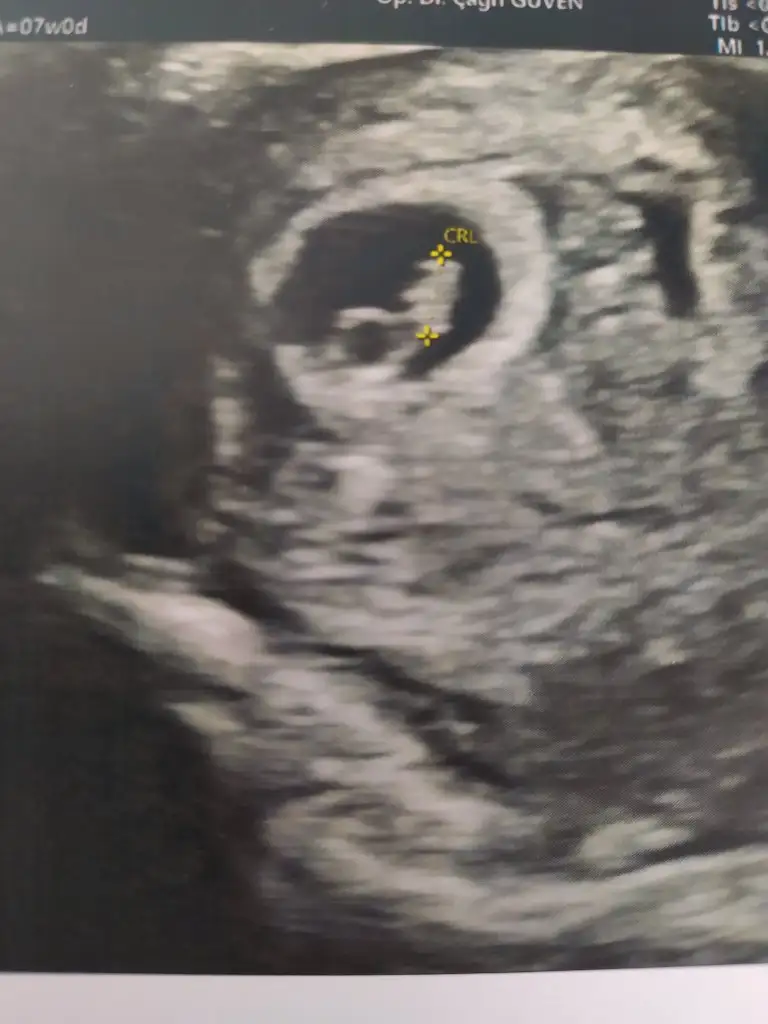

Evet karından gördük ancak kalp atışı çok zor duyuluyor, duyamazsanız panik yapmayın :)Merhaba ters rahim de 7 haftada karından goruluyir mu acaba ben de ayniyim

KızBana da bakabilirmisin canım 7+4 haftalik karından çekildi ultrason

Canım benimkini de tahmin edebilir misin